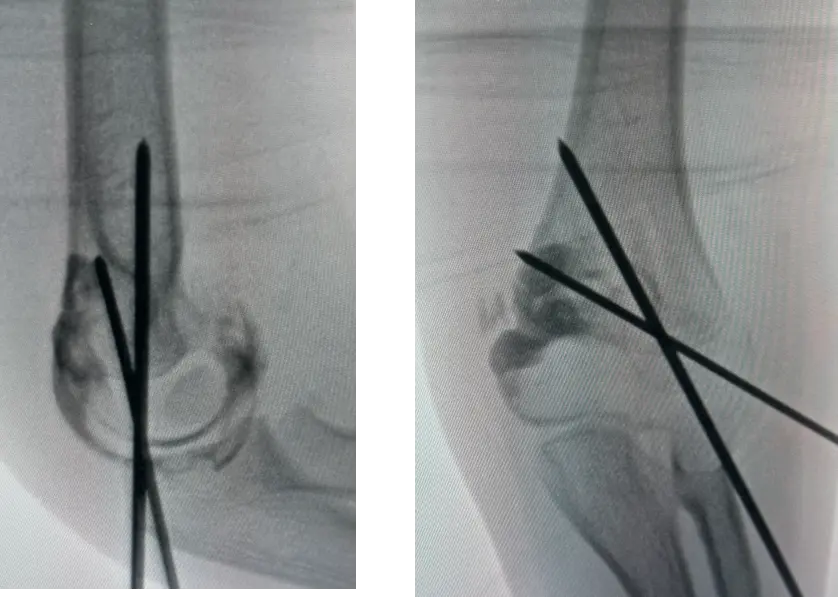

Displaced fractures:

- Closed reduction and fixation with K-wires & slab